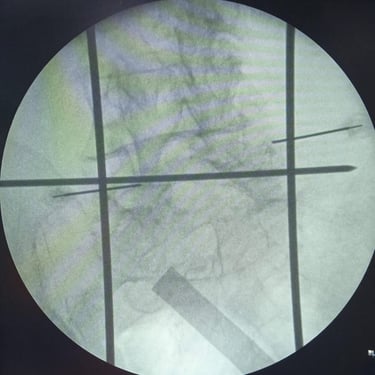

Fractura Lumbar Osteoporótica / Vertebroplastía y Bloqueo Lumbar Selectivo

La fractura lumbar osteoporótica y la artrosis lumbar son causas frecuentes de dolor crónico y limitación funcional en el adulto mayor. La osteoporosis debilita las vértebras, favoreciendo fracturas incluso ante esfuerzos mínimos, mientras que la artrosis genera desgaste articular e inflamación. La vertebroplastía percutánea permite estabilizar las vértebras fracturadas mediante la inyección de cemento óseo, proporcionando alivio rápido y mejorando la movilidad. En casos de dolor persistente por artrosis, el bloqueo lumbar selectivo ayuda a reducir la inflamación y el dolor. Ambas técnicas son procedimientos mínimamente invasivos que mejoran la calidad de vida y facilitan la recuperación funcional.